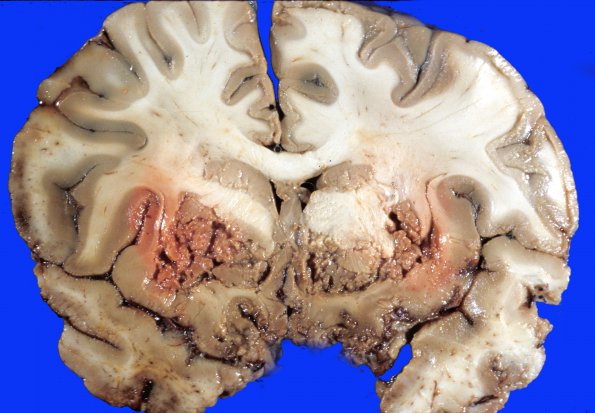

Coronal sections through the cerebral hemispheres show diffuse dusky greyish red discoloration of the cerebral cortex and the white matter of the centrum semiovale and internal capsule. The deep grey structures of the basal ganglia and thalamus are violaceous and granular with fragmentation, probably induced during sectioning. The dorsal aspects of the hemisphere appear better preserved.